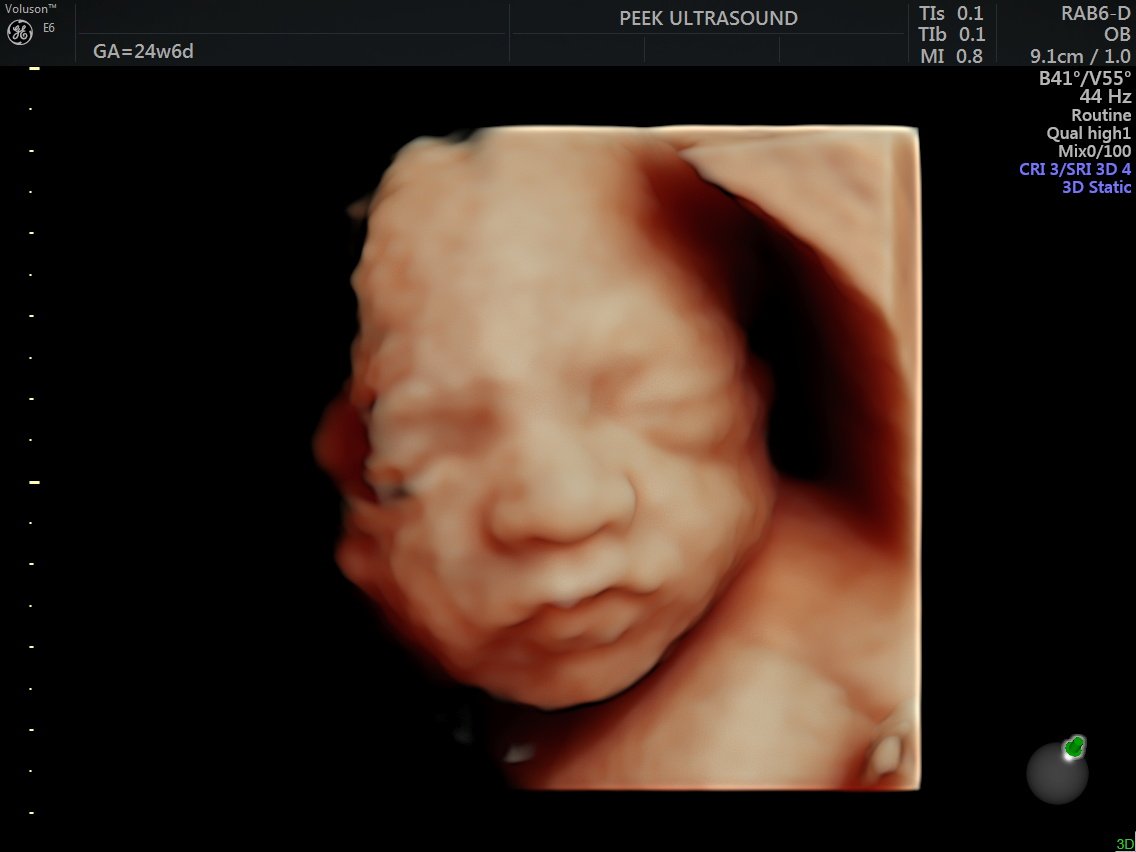

• 15-minute 2D/3D/4D/HD scan

• 14 to 26 weeks pregnant

• Incredible visuals with the latest 3D/4D/HD technology during the 2nd trimester

• Heartbeat measurement

• Witness it all in real time (blinks, yawns, smiles, etc.)!